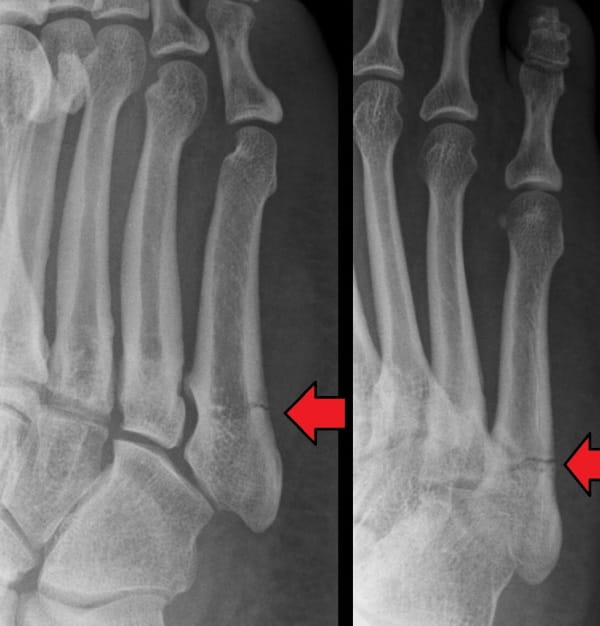

After he injured his foot while dancing, he requested an x-ray and diagnosed a fracture and not damage to the tendon, as he had first suspected. Finding similar fractures in several of his patients, he published his findings in the Annals of Surgery in 1902. What became known as the Jones fracture is a break between the base and middle part of the fifth metatarsal bone of the foot. Onset is usually sudden and is generally treated by immobilising the foot in a cast.

Cropped version of Jonesfracture.jpg, by Mdscottis, from Wikimedia Commons, licensed under the Creative Commons Attribution-Share Alike 3.0 Unported licence.